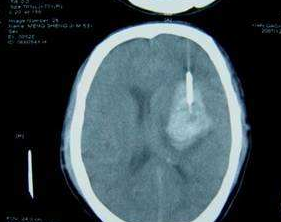

右頂部硬膜外血腫

右頂部硬膜外血腫參考資料